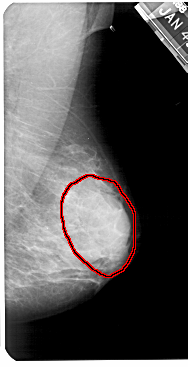

FILE: A_1425_1.RIGHT_MLO.OVERLAY

TOTAL_ABNORMALITIES 1

ABNORMALITY 1

LESION_TYPE MASS SHAPE OVAL MARGINS OBSCURED

ASSESSMENT 4

SUBTLETY 3

PATHOLOGY BENIGN

TOTAL_OUTLINES 1

BOUNDARY